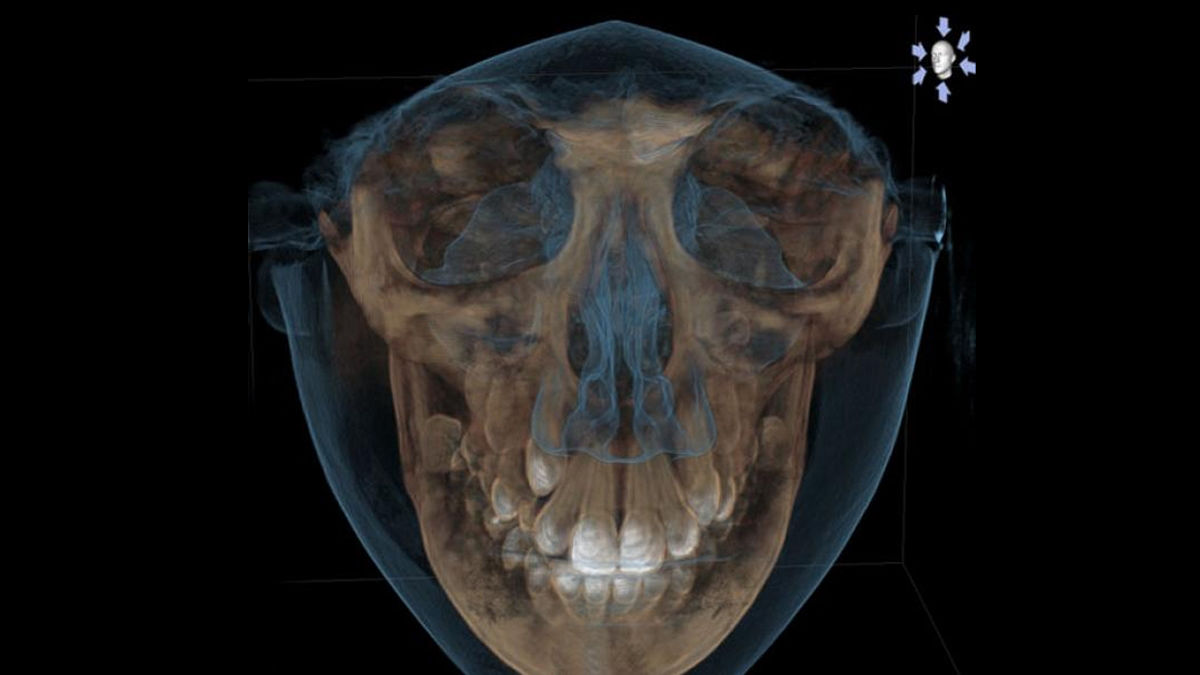

Facescanner

Mientras se obtienen las imágenes DICOM de rayos X, los sensores del Facescanner genera en formato STL la superficie facial del paciente.

El aparato de rayos X y el escáner facial 3D se superponen completamente de forma automática y exacta.

Esta ilustración realista hace que las sugerencias de tratamiento sean más comprensibles para los pacientes  construyendo así una mejor comunicación.